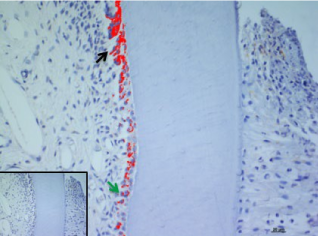

In the present study, we considered the histological, histochemical, and immunohistochemical changes stimulated by orthodontic tooth movement. The latter creates compression and tension areas with the following histological features: fibroblasts and fibrillar collagen were radially oriented, the PDL fibers appear narrow and extremely compacted with fibers disoriented both on the tension and compression sides, polynucleate osteoclast cells were also detected only on the compression side. Herein, a moderate vacuolization of the odontoblastic layer (green arrow) near to the pulp tissue, with MacroH2A.1 cells immunolabelling (black arrow) (Figure 1). The alveolar bone showed the presence of enlarged marrow spaces, on the compression side within scattered immunolabelled cells (black arrows) (Figure 2). The % of stained areas by MacroH2A.1, and densitometric count (pixel2), exhibited by dark brown pixels of the tested fields, in the compression side, were considered and compared to MacroH2A.1 immunoexpression of the tension side (Chart 1). From densitometric count, immunoexpression of MacroH2A.1 on the PDL compression side was strongly demonstrated (red color), as in the alveolar bone and in particular in osteoclastic cells (black arrows) (Figure 3). Moreover, densely and packed narrow PDL round cells were immunodetected on the compression side showing a strong MacroH2A.1 immunoexpression with a high % of stained areas respect to the tension side (p<0.001) (Figure 4). Negative controls showed no immunolabelling.

Figure 1. MacroH2A.1 immunoexpression on the compression side of tooth section. Green arrow indicate a moderate vacuolization of odontoblastic layer (OB), black arrow evidence MacroH2A.1 odontoblasts immunolabelling. Amplification: 40X; scale bar: 20μm. 113x85mm (300 x300 DPI)